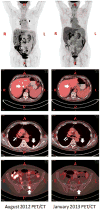

A posteriori evidence suggests that radiotherapy to a targeted tumor can elicit an immune-mediated abscopal (ab-scopus, away from the target) effect in non-targeted tumors, when combined with an anti-cytotoxic T-lymphocyte antigen-4 monoclonal (CTLA-4) antibody. Concurrent radiotherapy and ipilimumab (a human monoclonal anti-CTLA-4 antibody) induced immune-mediated abscopal effects in poorly immunogenic pre-clinical tumor models and metastatic melanoma patients. However, no such reports exist for patients with metastatic lung adenocarcinoma. We report the first abscopal response in a treatment-refractory lung cancer patient treated with radiotherapy and ipilimumab. A post-treatment increase in tumor-infiltrating cytotoxic lymphocytes, tumor regression, and normalization of tumor markers was observed. One year after treatment with concurrent radiotherapy and ipilimumab the patient is without evidence of disease.